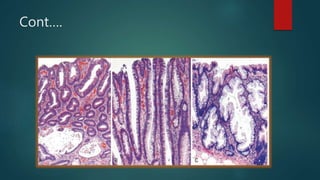

Adenoma-Carcinoma Sequence

 Colorectal adenomas are characterized by presence of epithelial dysplasia.

 Hallmark-nuclear hyperchromasia, elongation and startifiaction.

 Reduction in number of goblet cells.

 Tubular,tubulovillous or villous.

 Sessile serrated lesions-lack typical cytologic features of dysplasia.

 Size is the most imp risk of malignancy.